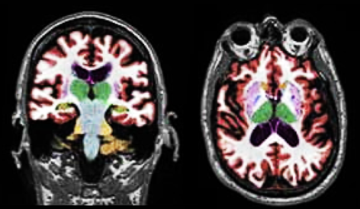

Alzheimer's Disease Clinical Decision Support Tool

A new project for 2020-2021, an SCU team is collaborating with CorTechs Labs, a medical imaging and genetics AI company, to support the development of clinical decision support tools for Alzheimer's Disease. Increasingly, data science techniques are being deployed to aid physicians with the increasing complexity of diagnostics and patient care. One element of these tools is the machine learning algorithms that drive the decision-making process. The other key element consists of a user interface for physicians. There is much need for a supportive tool to serve non-specialists who need to make a confident diagnosis that is dependent upon numerous and multi-faceted data. One such area is in diagnosing memory disorders. Students will build a tool that synthesizes a range of medical data to classify a patient on the Alzheimer’s disease spectrum.